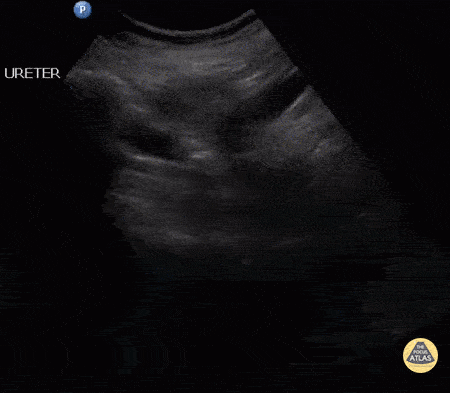

Renal/GU - Distal Ureteral Stone

A female patient presented with right flank pain. A longitudinal view of the lower ureter reveals a distal ureteral stone. Further ultrasound of the right kidney depicted medullary nephrocalcinosis. Image courtesy of Robert Jones DO, FACEP @RJonesSonoEM Director, Emergency Ultrasound; MetroHealth Medical Center; Professor, Case Western Reserve Medical School, Cleveland, OH View his original post here